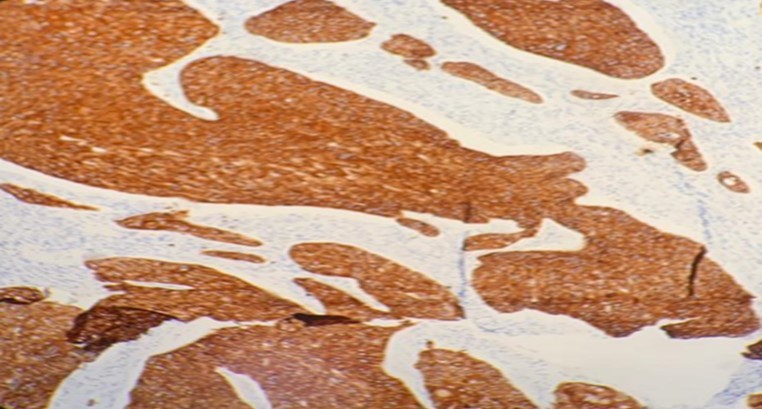

A 42-year-old gentleman, ex-smoker with underlying diabetes mellitus came to our clinic for right neck swelling for about 10 months. The swelling was gradually increasing in size and was giving occasional pain to the patient. But, there were no obstructive symptoms nor a history of prior exposure to radiation. Upon examination, there was a 2x2cm firm, fixed and non-tender swelling palpable at level II of right neck, with no skin changes seen. The facial nerve was intact and the oral cavity was clear. Proceed with flexible scope, there was no mass seen, and laryngeal structures were normal. Fine needle aspiration revealed normal salivary gland elements. A contrasted-CT scan reported a deep lobe parotid gland mass with non-opacification of the right internal jugular vein which could be from compression or thrombosis. [Figure 3] A wedge biopsy was performed subsequently which reported as squamous cell carcinoma, moderately-differentiated. [Figure 4, Figure 5 & Figure 6] Given the malignancy reported, a right total parotidectomy with right selective neck dissection was performed. Post-operatively, the patient developed House-Brackmann grade II facial nerve palsy. Histopathology showed evidence of squamous cell carcinoma with no involvement of adjacent nodes. A final diagnosis of T3N0M0 squamous cell carcinoma of the parotid gland was established. The patient was then referred to the oncology team for chemoradiation. Currently, the patient has completed adjuvant radiotherapy with no signs of recurrence observed so far at six months follow-up.

Figure 5.Photomicrograph show positivity to immunohistochemistry marker CK 5/6 in SCC of parotid (x20 high power field)

Meanwhile, for primary SCC lesions, the malignant cells show many cytoplasmic processes and desmosomes. Also, the cells have intermediate filaments in their cytoplasm with no secretory granules. These features usually help differentiate primary SCC from the similar-looking MEC. Moreover, SCC malignancies have distinct tumor markers that help pathologists in differentiating it from the rest of the tumors. These tumor markers are p40, CK 5/6 and p63. The use of these markers is as evident in this article.